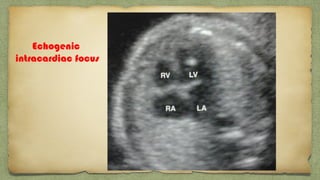

Echogenic

intracardiac focus